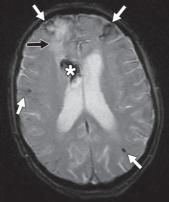

图 3A —患有线粒体脑肌病、乳酸性酸中毒和中风样发作 (MELAS) 的梗死患者的 MR 图像。T2 加权图像显示两个枕叶信号增加,右侧(粗箭头)大于左侧(细箭头)。

图 3B —患有线粒体脑肌病、乳酸性酸中毒和中风样发作 (MELAS) 的梗死患者的 MR 图像。弥散加权图像也显示双侧高信号,右侧(粗箭头)大于左侧(细箭头)。

图 3C —患有线粒体脑肌病、乳酸性酸中毒和中风样发作 (MELAS) 的梗死患者的 MR 图像。表观扩散系数图像(ADC)显示右侧信号减弱(粗箭头)但左侧信号正常(细箭头)。因此,右侧病变为急性梗死,弥散受限。左侧病变代表亚急性或慢性梗塞,弥散加权图像上有 T2 透过效应。

MRI 也可用于急性卒中,尽管技术和人员要求限制了它在许多中心的应用。DWI 是检测超急性梗塞(出现后 < 30 分钟)最敏感的序列,先于 CT(6 小时)和 T2 加权成像(6-12 小时)识别病情变化。急性梗塞中的扩散受限分别对应于 DWI 和 ADC 图上信号增加和减少的区域。随着梗死发展为亚急性和慢性阶段,会发展为血管源性水肿和脑软化症。这反映在 T2/FLAIR 信号强度的逐渐增加,且伴随着扩散系数的正常化(图3A ), 3B, 和3C)。也可以进行3D-TOF MRA或者3D-ASL检查。然而,与 CT 相比,空间分辨率较差,图像容易出现运动、磁化率和流动伪影。